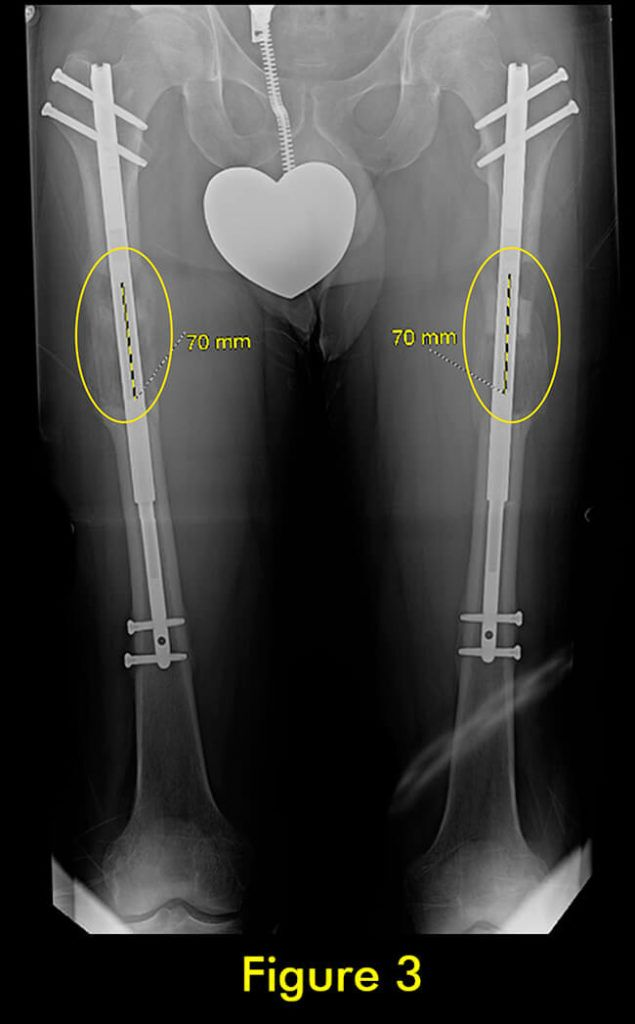

过早合并示意图1

图1:延长量细微差异

过早合并示意图2

图2:X光片确认诊断

随着胫骨的延长,腓骨也必须延长。植入式加长装置仅延长和固定胫骨。腓骨必须固定在胫骨上,以便它与胫骨一起拉长。如果腓骨固定不固定或固定不充分,它不会像胫骨那样拉长,并会导致严重的后果,包括脚踝半脱位和关节炎以及膝盖屈曲挛缩。

固定方法至关重要。许多外科医生只将腓骨的下端固定在胫骨上。这会导致腓骨过早巩固,并在其上端从胫骨向下拉和脱臼。固定腓骨两端很重要。大多数外科医生避免这样做,因为这在技术上很难做到。

我们为所有患者的腓骨两端固定。植入式加长时,腓骨必须用螺钉固定在胫骨上;上端有一个螺钉,下端有一个螺钉。螺钉的角度、水平、位置、直径和类型都很重要。一个常见的错误是将螺钉水平放入两块骨头之间。这不足以防止腓骨从脚踝处的胫骨上拉开。这是非常微妙的,即使脚踝腓骨长度的几毫米差异也会给患者带来短期和/或长期后果。切除腓骨的一部分以防止腓骨不分离是另一种应避免的常见方法。它会导致腓骨不愈合,从而导致胫骨以后出现应力性骨折。

此外,它通常不会阻止腓骨从胫骨上拉开。因此,腓骨并发症与植入式延长装置的类型无关,而是与外科医生选择将腓骨固定到胫骨的方法和切割腓骨的方法有关。腓骨愈合的范围可以从过早巩固到完全不愈合。后者通常不需要治疗,只要胫骨牢固愈合。前者需要重复腓骨截骨术。